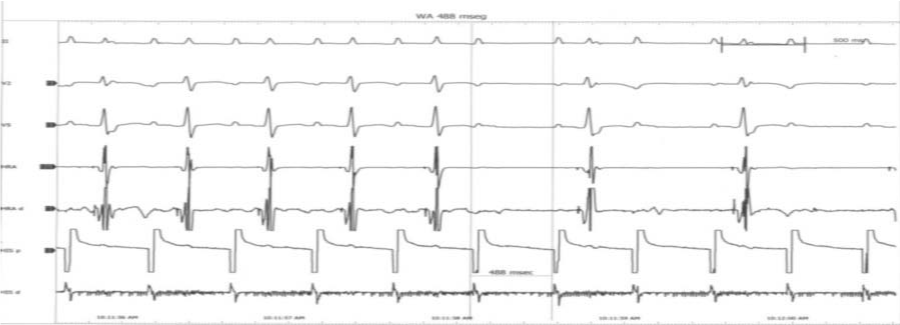

Figure 2 Patient in Supra-ventricular Tachycardia.

Figure 3 ECG was taken after administration of 12 mgs of Adenosine. Heart rate value is 67-68 beats per minute: Accelerated atrioventricular stimulation with an early and shortened ventricular repolarization. Can be seen a short PQ interval (<0120 seconds) with an early and shortened ventricular repolarization (QTc <0.350. seconds).

Both PQ and QT intervals are short (Figure 3-5).

Figure 5 Holter Image: Same features than Figure 1. PQ-interval: 0.100-0.110 seconds=Short PQ-interval. QTc (Bazzet) 0.339-0.340 seconds (< 0.350 seconds) = Short QT-interval. QTc (Fridericia) 0.332 seconds (< 0.350 seconds) = Short QT-interval.

PQ- interval: 0.10 - 0.11 seconds. RR- interval: 0.862- 0.900 seconds. QT- Interval:0.322-0.330 seconds. Bazett’s formula: 0.339-0.343 seconds. Fridericia’s formula: 0.330-.337 seconds.